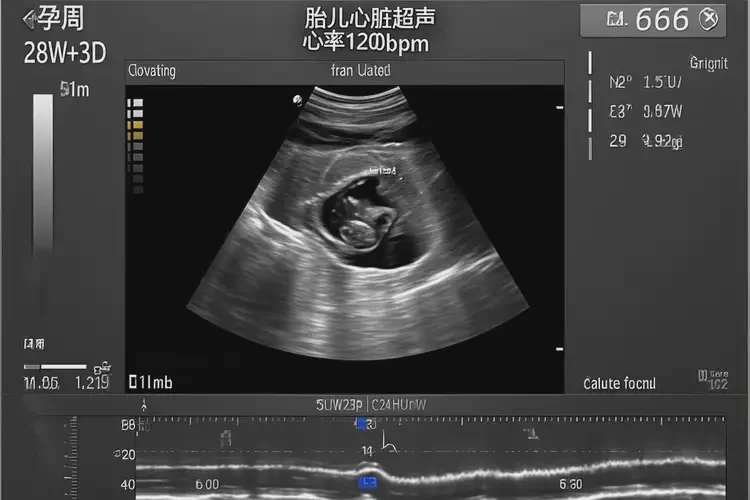

孕40周5天胎心率99有危險(xiǎn)嗎(圖1)

超聲檢查通過(guò)超聲圖像觀察胎兒心臟結(jié)構(gòu)和功能懷疑胎兒心臟問(wèn)題等情況